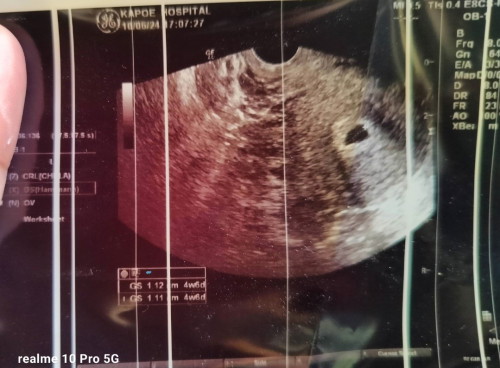

อัลตร้าซาวด์แบบนี้ปกติไหมคะ

หมออัลตร้าซาวด์ให้ตอน 4w 6d ผลอัลตร้าซาวด์เป็นแบบนี้ปกติไหมคะ แต่เรารู้สึกตำแหน่งถุงตั้งครรภ์มันแปลกๆ ใครเป็นแบบนี้บ้างไหมคะ 😅

น้อนยังเล็กค่ะ บางคน4สัปดาห์ยังไม่เห็นถุงตั้งครรภ์เลยค่ะ